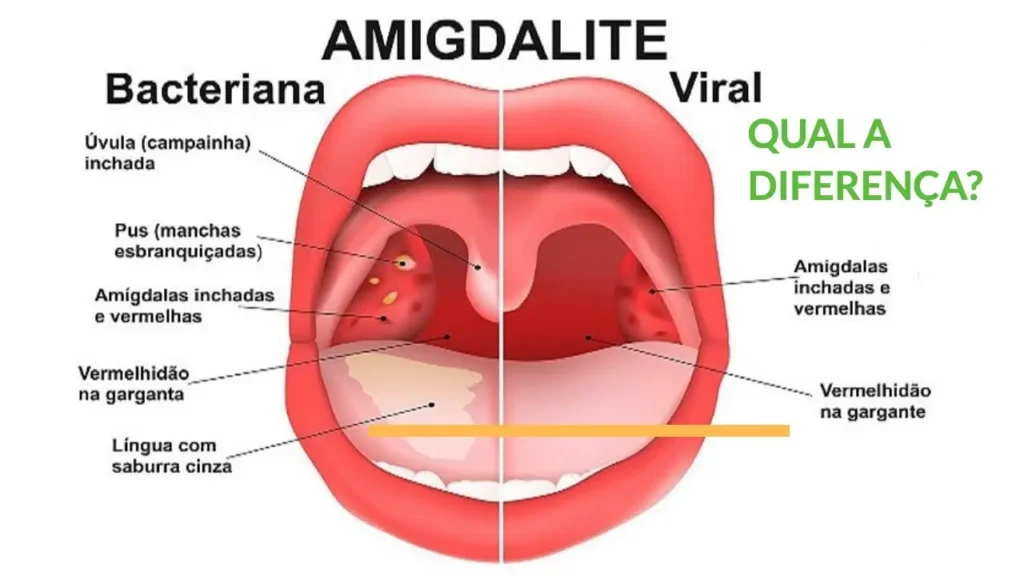

“Infecções virais, como gripes e resfriados, são a causa mais frequente de dor de garganta, enquanto a amigdalite bacteriana, menos comum, pode apresentar pontos de pus e febre alta.”

Infecções Virais e Bacterianas: O Duelo na Garganta

As infecções virais, como as do resfriado comum e da gripe, são as vilãs mais comuns. Elas costumam vir acompanhadas de outros sintomas, como coriza e tosse. Já as infecções bacterianas, como a estreptocócica, embora menos frequentes, exigem atenção especial, pois podem levar a complicações se não tratadas corretamente com antibióticos. A diferenciação é crucial para o tratamento.

Benefícios e Desafios Reais no Tratamento da Dor de Garganta

Os benefícios de tratar a dor de garganta corretamente são claros: alívio rápido do desconforto, recuperação da capacidade de se alimentar e falar sem dor, e prevenção de complicações. No entanto, os desafios existem. Um deles é diferenciar infecções virais de bacterianas, já que o tratamento difere. Outro desafio é lidar com a dor crônica ou recorrente, que pode indicar condições subjacentes que necessitam de investigação. A adesão a tratamentos, especialmente quando envolvem antibióticos, também é um ponto crucial.

Qual a diferença entre dor de garganta viral e bacteriana?

A dor de garganta viral geralmente vem acompanhada de outros sintomas como coriza e tosse, e melhora com repouso e hidratação. Já a dor de garganta bacteriana costuma ser mais intensa, com febre alta, dor ao engolir e, às vezes, presença de pus. Saber diferenciar é o primeiro passo para o tratamento correto.